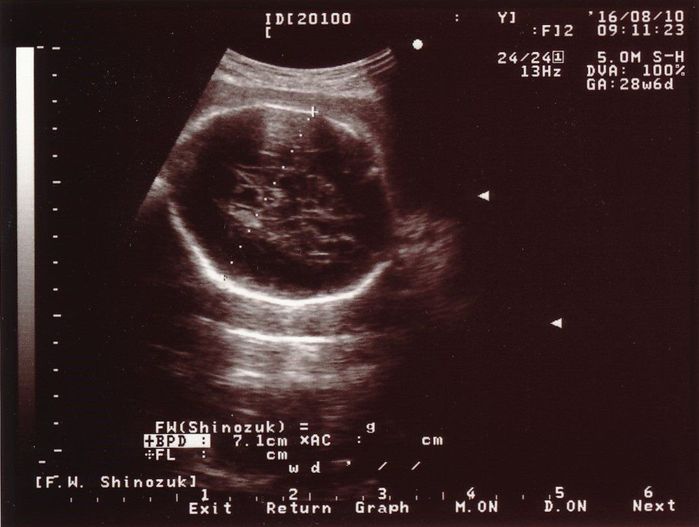

妊娠28週目のエコー写真

赤ちゃんの頭の大きさ(BPD)とお腹周り(AC)を測りました。赤ちゃんの成長は順調そのものでしたが、血液検査の結果で貧血の治療が必要となり、服薬はもちろんのこと、点滴のため週2回程度の病院通いが始まりました。